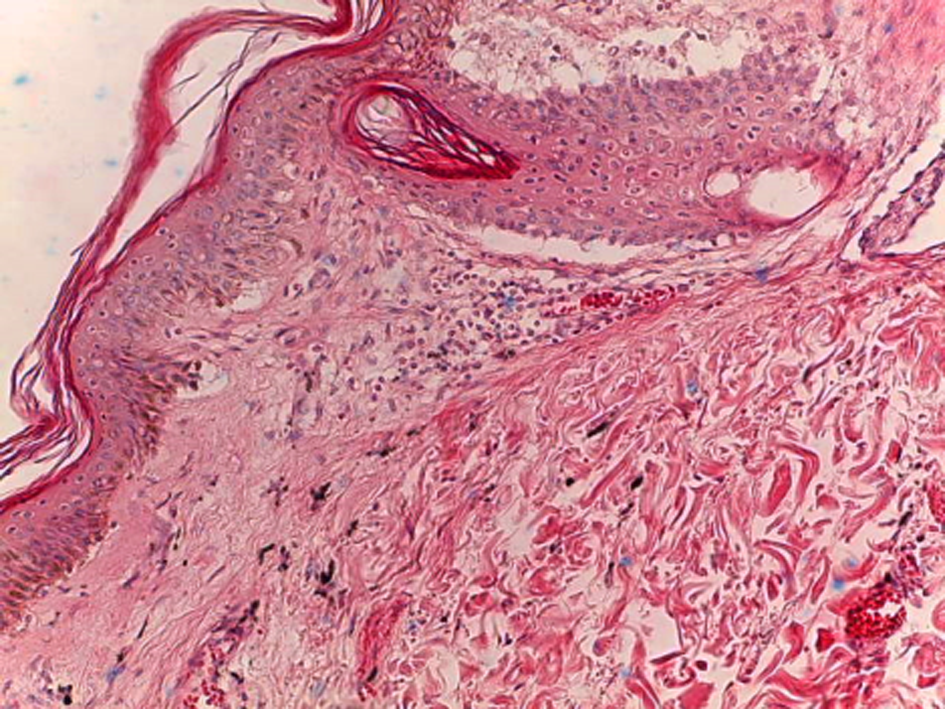

In all the skin samples in the groups with tattooing, the signs of the traumatic damage were reported in tattooing with a black pigment and an inflammatory reaction in response to this damage. When assessing the skin layers in the negative control group, the epidermis was characterized by preserving all its layers, where the epithelium was represented by a basal layer that was fairly tightly adjacent to the basement membrane without signs of damage.

The remaining layers of the epidermis (prickle-cell, granular, horny) were preserved and clearly visualized when stained with hematoxylin and eosin. In the papillary and reticular layers of the derma, an accumulation of the black pigment was reported. It was located both diffusely and perivascularly, which was accompanied by a reaction of the vascular bed and the development of a pronounced inflammatory reaction. So, in the early period, there was a slight perivascular edema and the presence of neutrophils mainly in the reticular layer of the derma. The boundary between the reticular and papillary dermal layers was not clearly detected due to the edema and inflammatory infiltration. The dermal fibers were more loose compared to the skin samples of the intact animals (Fig. 3).